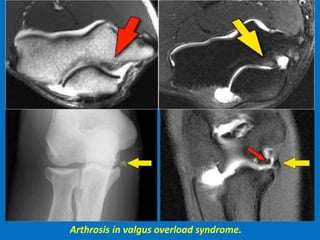

Valgus overload syndrome" with very characteristic injuries to the elbow over time.

The tension on the medial side causes a tear of the ulnar collateral ligament.

Compression on the lateral side causes an osteochondral lesion of the capitellum.

The shear forces on the posterior side cause arthrosis.

Arthrosis in valgus overload syndrome.

Valgus overload syndrome"with very characteristic injuries to the elbow over time. The tension on the medial side causes a tear of the ulnar collateral ligament. Compression on the lateral side causes an osteochondral lesion of the capitellum. The shear forces on the posterior side cause arthrosis.

Arthrosis in valgusoverload syndrome.